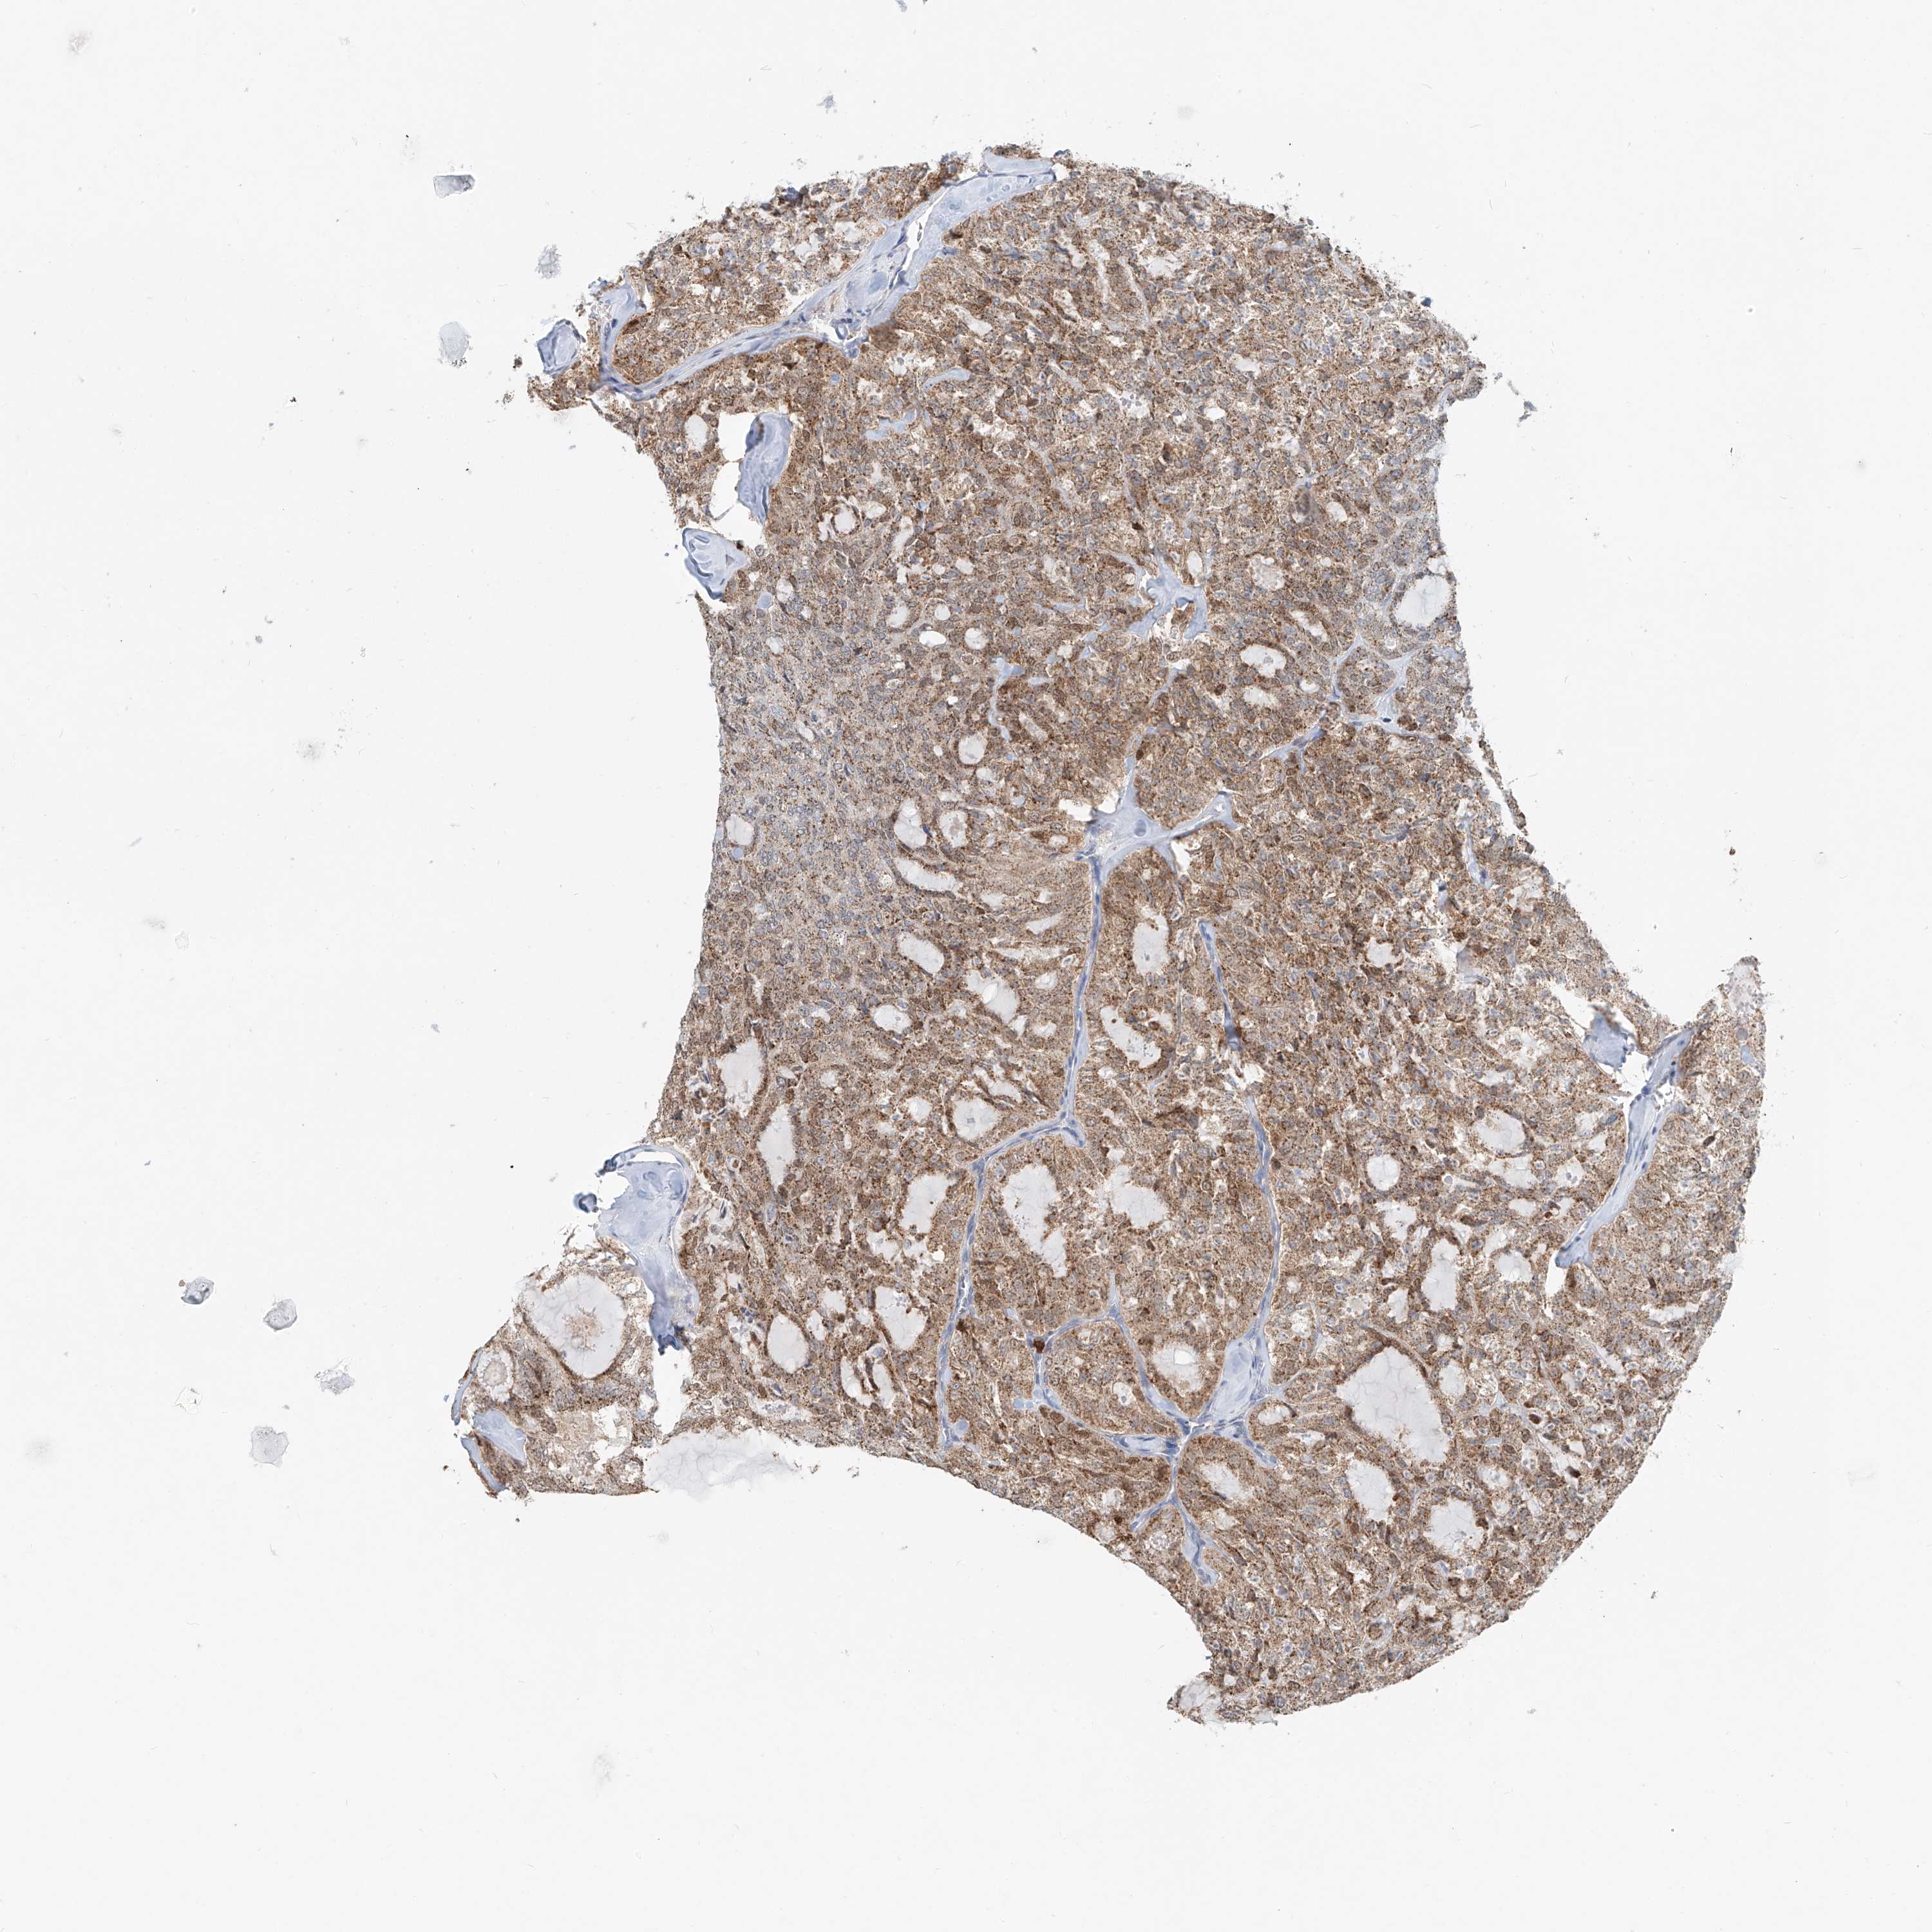

THYROID CANCER - Protein expressioni

A mouse-over function shows sample information and annotation data. Click on an image to view it in a full screen mode. Samples can be filtered based on level of antibody staining by selecting one or several of the following categories: high, medium, low and not detected. The assay and annotation is described here.

Note that samples used for immunohistochemistry by the Human Protein Atlas do not correspond to samples in the TCGA dataset.

Antibody stainingi

Antibody staining in the annotated cell types in the current human tissue is reported as not detected, low, medium, or high, based on conventional immunohistochemistry profiling in selected tissues. This score is based on the combination of the staining intensity and fraction of stained cells.

Each image is clickable and will lead to virtual microscopy that enables deeper exploration of all samples and also displays staining intensity scores, fraction scores and subcellular localization as well as patient and tissue information for each sample.

Antibody HPA029412

Antibody CAB034366

Staining

High

Medium

Low

Not detected

Intensity

Strong

Moderate

Weak

Negative

Quantity

>75%

75%-25%

<25%

None

Location

Nuclear

Cytoplasmic/membranous

Cytoplasmic/membranous,nuclear

Papillary adenocarcinoma, NOS

Follicular adenoma carcinoma, NOS